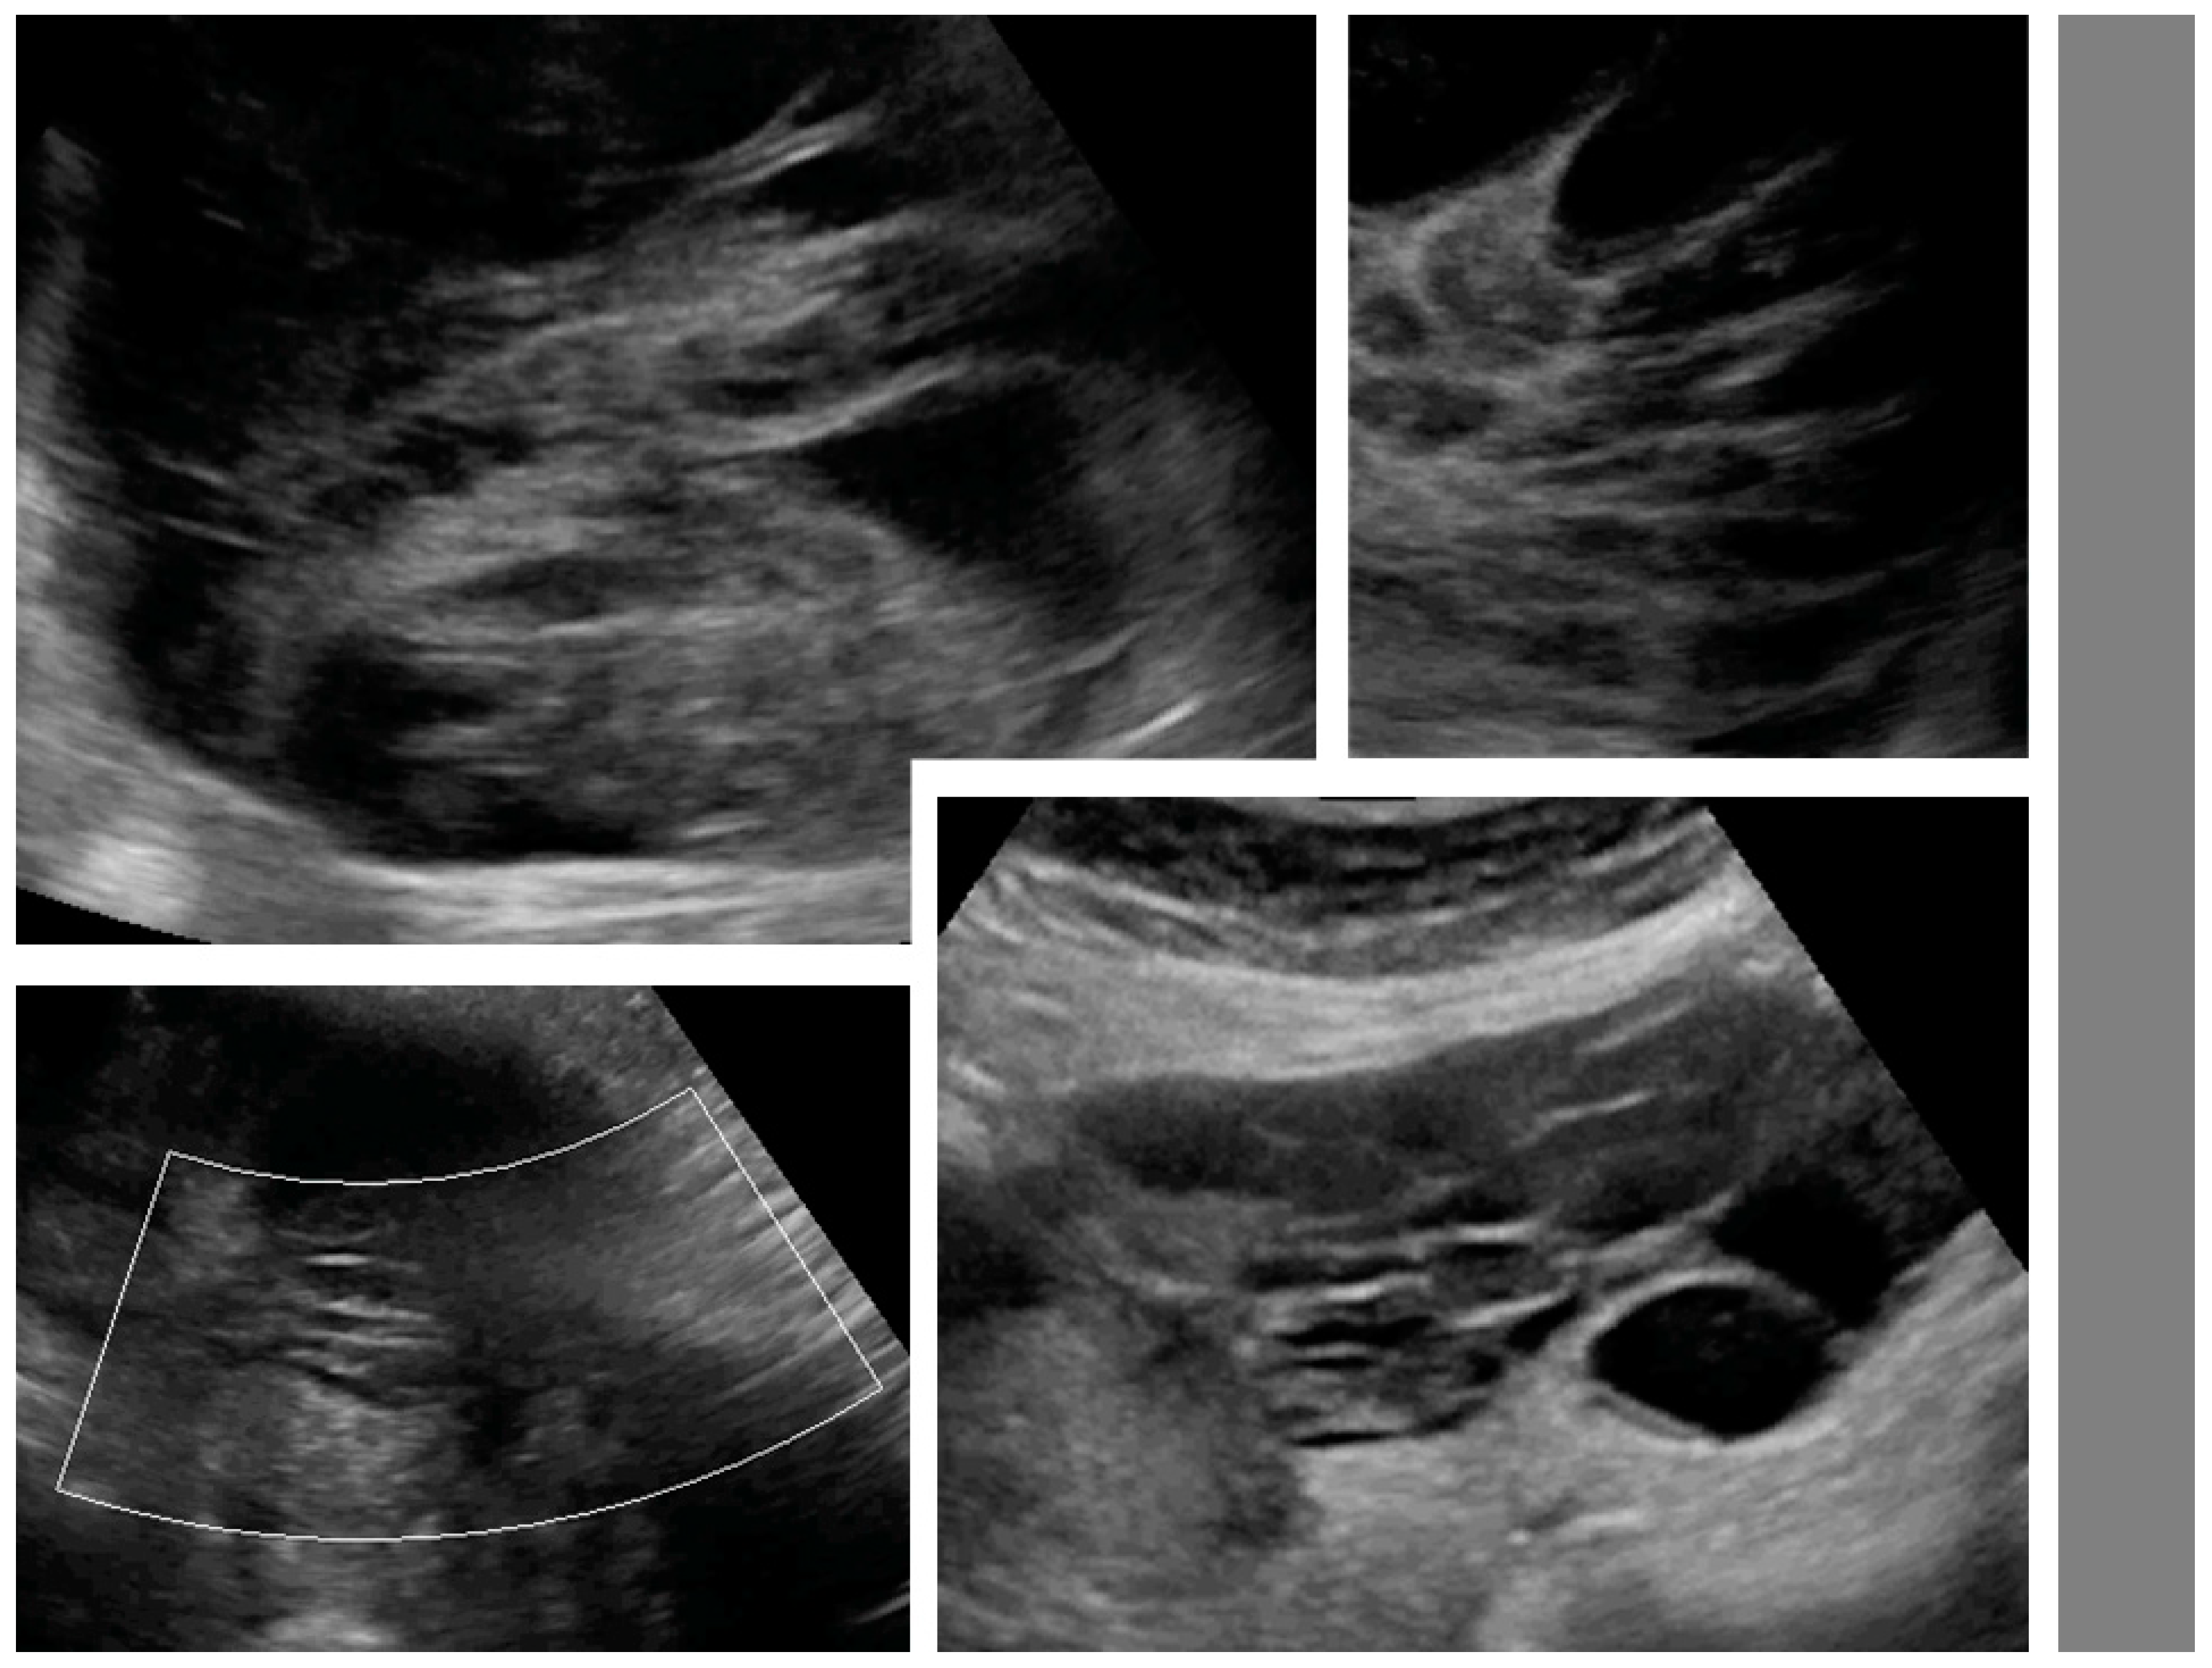

Figure 2.

Necrosis sign [7] in tumor solid portions. Arrows indicate area suspected for necrosis. White dotted line is a measurement of the tumor.

Figure 3.

Layered structure of multilocular tumors.

Figure 4.

Solid papillary projections (arrows) growing from the septa and inner wall. White dotted lines are measurements of the tumor.

Upon ultrasound examination, ovarian mCRC were mostly solid (43%), multilocular-solid (45%), unilateral (61%), or mobile or semi-fixed (70%), with the median largest tumor and solid component diameters of 94 and 67 mm, respectively. Necrosis was noted in 49% of lesions (Figure 2). A layered structure was noted in tumors with cystic components (Figure 3), most of which had more than five locules (Figure S3, Video S2) and solid papillary projections growing from the septa, or the septa and inner wall (Figure 4). Most tumors were vascularized (84%), with moderate to marked blood flow detected in 53% of cases. On abdominal ultrasound scans for disseminated disease, metastases were detected in 46% of cases and classified as omental cake (46%), peritoneal carcinomatosis (46%), parenchymal liver metastases (27%) (Figure S4), and other (32%). Ascites was detected in 32% of women.